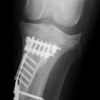

術後左後肢側面像

術後左後肢正面像

術前のTPAは左後肢33.1°右後肢26.8°でしたがTPLO実施により左後肢5.5°右後肢12°に矯正されました。